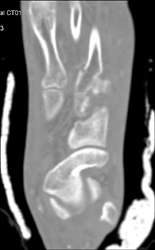

DIEP Flap Planning